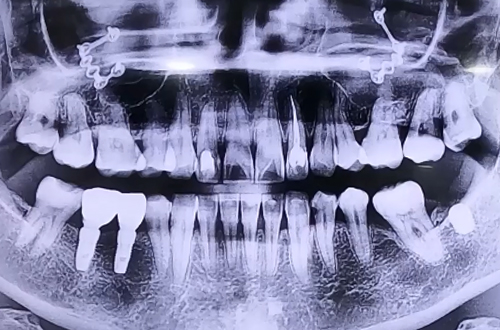

BEFORE

오른쪽 아래 임플란트 보철을 완성하고 최근에는 왼쪽도 임플란트를

진행하면서 신경에 닿지 않도록 실시간으로 확인하며 진행해 드린 환자분이십니다.

수술시간은 다른 환자분들보다 조금 더 걸리는 수술이었지만 하치조 신경에

닿지 않고 안전하게 수술하는 게 가장 중요했던 케이스입니다.

임플란트를 심어드린 다음 잇몸뼈가 부족한 부분은 뼈이식을 통해 단단하게 마무리해 드렸습니다.